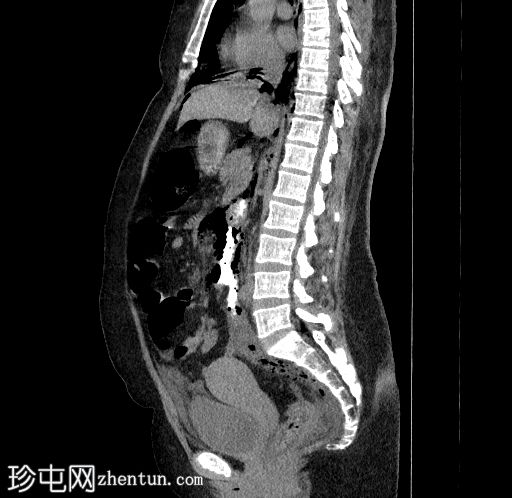

5.jpg

矢状位

口服增强

食管下三分之一处管壁均匀增厚,可见气泡(穿孔起始部位),纵隔及双侧胸膜腔内可见游离气体,提示食管穿孔。

十二指肠内可见造影剂早期渗漏至十二指肠旁间隙(第二个穿孔部位),同时主动脉旁、结肠旁、肾周及膈下区域可见游离气体,提示十二指肠穿孔。

CT扫描提示医源性食管损伤及十二指肠穿孔,导致大量气胸和气腹。